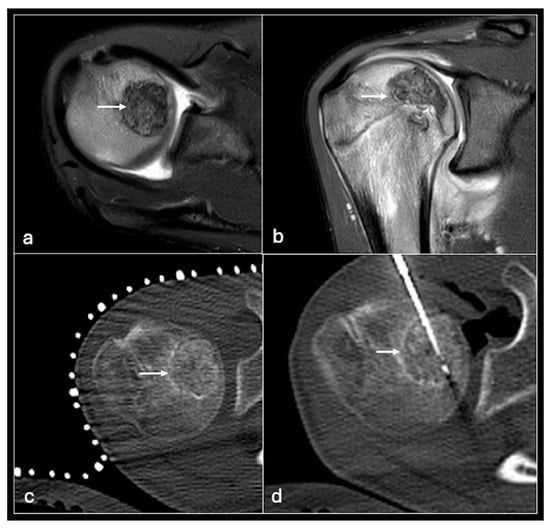

Figure 12. STIR axial (a), coronal (b) showing chondroblastoma in the humeral head (arrow) treated with CT-guided cryotherapy (c,d).

Cryoablation is the direct rapid cooling of lesions to temperatures as low as −100 °C to induce crystallisation of intracellular water thus causing apoptosis. This is achieved using rapidly expanding gas (usually argon) to cause a rapid drop in temperature via a phenomenon termed the Joule–Thompson effect [50]. Multiple freeze–thaw cycles are usually required with the latter achieved using helium gas infusion (Figure 12).

Indications are more wide-ranging than other forms of ablation. Curative oncological indications include benign desmoid tumours, osteoid osteomas, vascular malformations, aneurysmal bone cysts and neuromas [50,51]. Malignant lesions such as bone metastases can be treated curatively but palliation of painful bone metastases is a more established process [52,53,54].

Like other thermoablation methods, cryoablation is achieved by percutaneously inserting probes into the lesion. Unlike RFA, multiple needles can be used allowing more flexibility in tumours of different geometry and coverage of a larger ablation area. However, the ablation process takes longer and is more expensive than other options. As well as general thermoablation risks to the skin and perilesional structures, specific risks include cryomyositis (peritumoural muscle inflammation) and cryoshock (a systemic inflammatory response from the release of inflammatory mediators). Numerous methods can be employed to minimise inadvertent freezing risk such as hydrodissection and active or passive warming of the adjacent structures [33,55]. Temperature monitoring and direct visualisation of the ice ball using CT or ultrasound during cryotherapy can also reduce the risk of injuring adjacent structures [56,57].